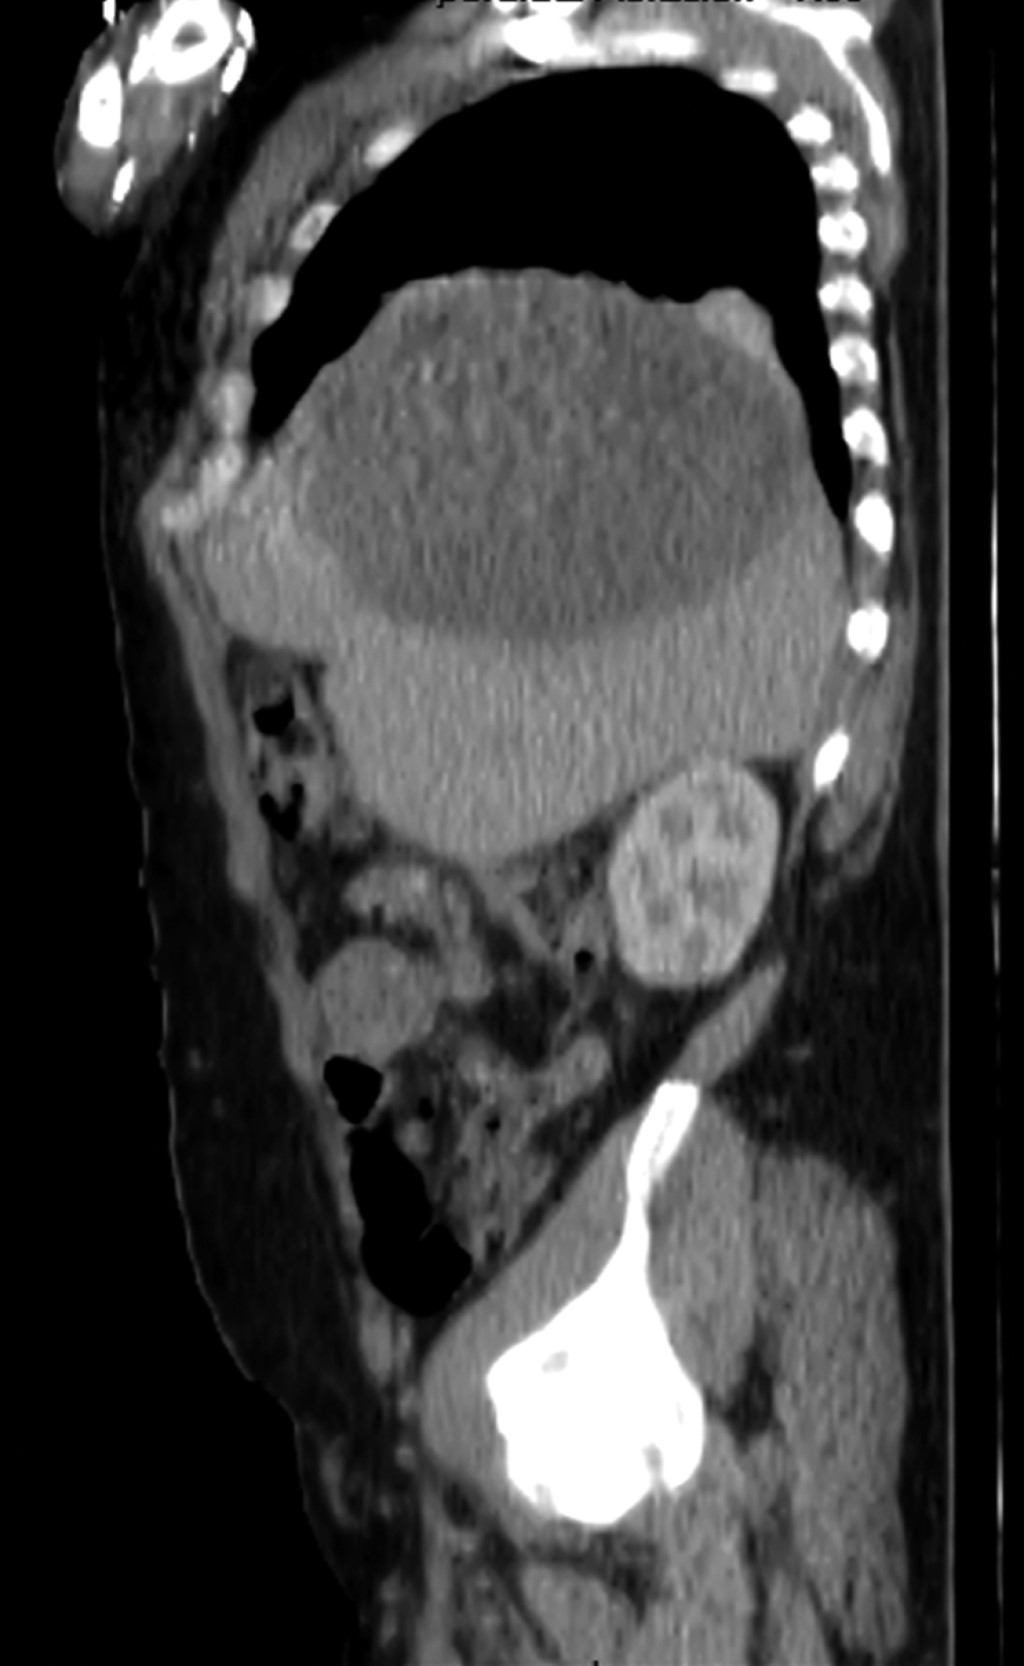

A su ingreso se mostraba ansioso, alerta, orientado; valoración inicial ATLS (Advanced Trauma Life Support), sin compromiso hemodinámico, neurológicamente sin déficit, tórax con dermoabrasiones, campos ventilados de manera bilateral, hipoventilación basal de hemitórax derecho, abdomen con marcas cutáneas de neumáticos, blando, depresible con dolor a la palpación generalizada profunda, datos de irritación peritoneal en cuadrantes inferiores, extremidades con dermoabrasiones en antebrazos. Se realizan placas de protocolo de ATLS, se observó en la radiografía de tórax (Figura 1) hemitórax derecho con elevación del hemidiafragma, sin neumotórax o derrame pleural, se efectúa FAST (Focused Abdominal Sonography for Trauma) primario sin revelar líquido en pericardio, espacio hepatorrenal, esplenorrenal o en pelvis, se realiza tomografía axial computarizada simple y contrastada toraco-abdomino-pélvica (Figuras 2 y 3) en la que se observa imagen compatible con quiste hepático simple de 12.6 x 14.7 cm.

Figura 1